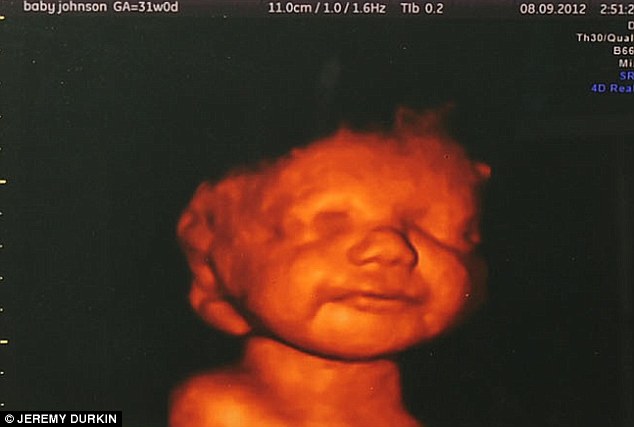

| Рождение улыбки О. Мандельштам

***************

Когда заулыбается дитя

С развилинкой и горести и сласти,

Концы его улыбки, не шутя,

Уходят в океанское безвластье.

Ему невыразимо хорошо,

Углами губ оно играет в славе -

И радужный уже строчится шов

Для бесконечного познанья яви.

На лапы из воды поднялся материк -

Улитки рта наплыв и приближенье -

И бьет в глаза один атлантов миг:

Явленья явного в число чудес вселенье.

И цвет и вкус пространство потеряло,

Хребтом и аркою поднялся материк,

Улитка выползла, улыбка просияла,

Как два конца их радуга связала,

И в оба глаза бьет атлантов миг.